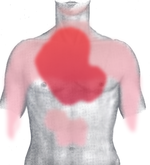

Rough diagram of pain zones in myocardial infarction (dark red = most typical area, light red = other possible areas, view of the chest).

Back view.

يسبب احتشاء العضلة القلبية وهو ألم حاد في منتصف الصدر يوصف بأنه عاصر أو طاعن أو ضاغط أو ضيق شديد بالصدر وهو يماثل ألم الخناق الصدري ولكنه يتميز عنه ب

- يحدث بجهد أو بدون جهد

- شدته أكبر وقد يدوم لساعات

- لا يزول بالراحة ولا باعطاء النيترات

الألم يمتد عادة إلى الذراع الأيسر ولكنه قد يمتد إلى الرقبة والفك السفلي الكتف الذراع الأيمن الظهر أو الشرسوف يترافق مع أعراض التعرق الشديد البرودة الخفقان الغثيان الإقياء أو الشعور بالدوار